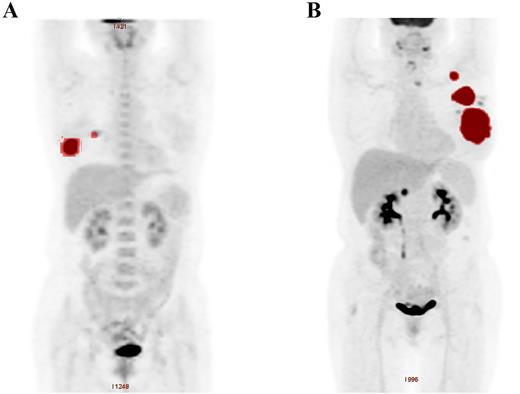

In the whole population, the median TMTV0 was 87 cm3 (range: 3-312 cm3). The ROC analysis showed that the optimal TMTV cut-off value for estimating PFS and OS was 90 cm3. The areas under the curves (AUCs) were 0.767 for PFS and 0.719 for OS. The sensitivities and specificities were 73.6% and 77.2% for PFS, and 71.3% and 73.2% for OS respectively. The prognosis of patients with high TMTV0 (TMVT0 > 90 cm3, n = 44) was significantly worse, with 5-year PFS and OS of 44.5% and 62.3%, respectively, while those with low TMTV0 (TMVT0 ≤ 90 cm3, n = 50) were 74.8% and 84.9% (P = .005 for PFS and P = .017 for OS). In multivariate analysis, TMTV0 also remained a more reliable predictor of survival than other prognostic factors including TLG (TMTV0: P < .001 for PFS and OS; TLG: P = .003 and P = .002 for PFS and OS individually). In this study, we also demonstrated that baseline high serum β2-microglobulin level and ECOG performance status predicted both shorter PFS and shorter OS.

We then constructed a new prognostic model of PBL based on serum β2-microglobulin level, ECOG performance status in combination with TMTV0. According to whether there are adverse factors, we divide patients into four risk categories. The prognosis of the four groups was significantly different, with 5-year PFS of 86.9%, 62.5%, 38.6 and 19.3% (P = .001) and 5-year OS of 92.4%, 70.6%, 52.1% and 29.4 (P = .013), respectively.